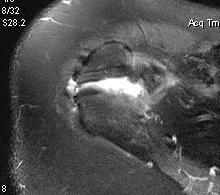

X-ray

Best seen on axillary lateral

Axillary lateral showing meso-acromion Scapula lateral xray showing os acromiale